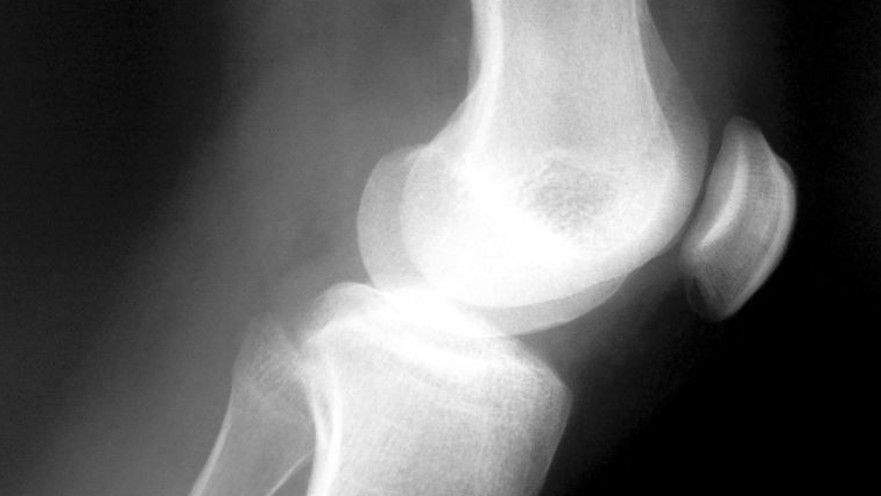

כאבי צמיחה אצל ילדים. הסבר וטיפים לעזרהבמרכז הרפואי בני ציון חקרו ומצאו שבין 25%-40% מהילדים סובלים מזה. מנהל מחלקת אורטופדיה מסבירמעריב אונליין13:44 04/05/2016כואב בגדילה | צילום: SXCתגיות:בריאות/ הורים וילדים/ בית חולים